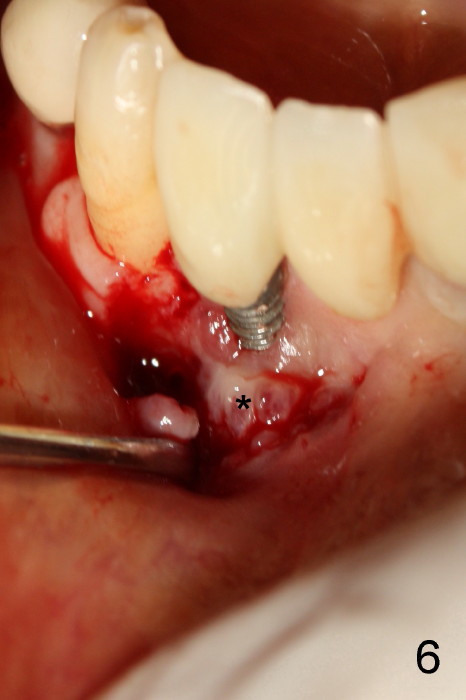

The patient has had chronic pain and swelling associated with the implant at the site of #26 (Fig.1). The extent of implant thread exposure is shown in Fig.2 after flap reflection; inflammatory granulation tissue is present around the most coronal threads (*, one year post cementation). Following debridement and Clindamycin soaking, allograft is placed around the exposed threads; a titanium mesh is used to contain the graft (Fig.3). The flap is closed with tension in spite of the periosteum being underscored. The patient develops moderate to severe ecchymosis postop.

The coronal portion of the mesh is exposed with loss of bone graft granules. It appears that the mesh has lost its function. It is planned to be removed. PA is taken 16 days post placement of the mesh (Fig.4).

Fig.5 is taken following local anesthesia to show the exposed mesh, 22 days post placement. When the latter is removed, the exposed threads appear to be less (Fig.6, as compared to Fig.2). There is healthy granulation tissue growth apically (*). The patient is asymptomatic 1 month post mesh removal; there is no tenderness around exposed threads (Fig.7). Connective tissue graft is planned to cover the exposed threads through tunnel technique. Thread exposure appears less 3 months post mesh removal (Fig.8). There is infection when the region is not kept clean (Fig.9 (2.5 years post mesh removal)). The other 1-piece implant should have minor implant exposure (<). It appears that there is no thread exposure associated with the immediate implant at #28. Using smaller 1-piece implants (2.5 or 2.0 vs. 3 mm) with flap surgery should be able to prevent the complication. The 72-year-old phobic patient declines any further treatment. Two years later, she agrees to have treatment because of repeated infection (Fig.10). Impression has been taken for stent. After sectioning FPD and removing the infected implant (Tatum), a smaller implant will be placed in between the implants. If her vein is not too small, blood will be drawn for PRF.